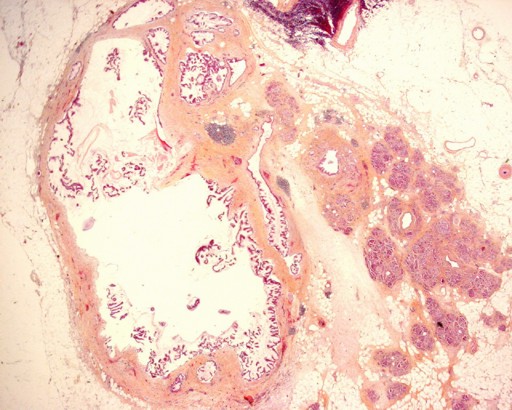

A 56-year-old man was admitted to our hospital for recurrent pancreatitis. Noteworthy aspects of his medical history included alcohol and tobacco consumption, an ischemic stroke related to right carotid aneurysmal rupture and hypertension. Following the stroke, he suffered from left hemiplegia and epilepsy. Although he no longer consumed alcohol, he had been treated for two episodes of acute pancreatitis during the previous year. He complained of epigastric pain at the time of the consultation (his medical treatment included 40 mg of morphine orally per day) and, upon physical examination, he was found to have left hemiplegia without jaundice, fever or weight loss. Abdominal palpation did not detect any abnormal mass and laboratory examination revealed no hyper-leucocytosis or anemia. Hepatic and pancreatic enzymes were slightly increased (ALT: 52 IU/L, reference range: 0-41 IU/L; AST: 43 IU/L; reference range: 0-38 IU/L; lipase: 264 IU/L, reference range: 114-286 IU/L; amylase: 100 IU/L; reference range: 25-115 IU/L), but there was no biological cholestasis. An abdominal CT scan showed a polycystic lesion, 26 mm in diameter, located in the uncus. This lesion was associated with a concurrent stenosis of the isthmic pancreatic duct which resulted in a distal dilation (Figure 1). Following an endoscopic ultrasound and MRI, the cystic lesion was characterized as a typical branch-type IPMT and the ductal dilation was attributed to chronic pancreatitis (Figure 2). The final diagnosis was, therefore, of chronic pancreatitis related to an IPMT of the uncus. A surgical resection of this IPMT was carried out. A Whipple procedure was then performed with extemporaneous histological analysis of the pancreatic cut edge, revealing the presence of malignant cells. In view of these histological findings, the pancreatic incision was shifted 3 cm to the left of the pancreatic isthmus, revealing no malignant cells upon extemporaneous histological analysis. Definitive histological analysis confirmed the diagnosis of an IPMT in the uncinate process (Figure 3) as well as a concurrent adenocarcinoma, 1 cm in diameter, located 2 cm from the primary IPMT, in the isthmus (Figure 4). The patient had an uneventful postoperative course and was discharged from the hospital 15 days following surgery. The patient subsequently underwent adjuvant chemotherapy. He is alive without recurrence 7 months following the surgery. Upon postoperative review of the original CT scan, we noted that the stenosis which was initially attributed to chronic pancreatitis was, instead, due to a lesion that we had not originally identified and which corresponded to the concomitant adenocarcinoma.

Figure 3. Histological findings: pancreatic ducts lined by tall, columnar, mucin-containing epithelium with papillary projections representing an IPMT (x10). |